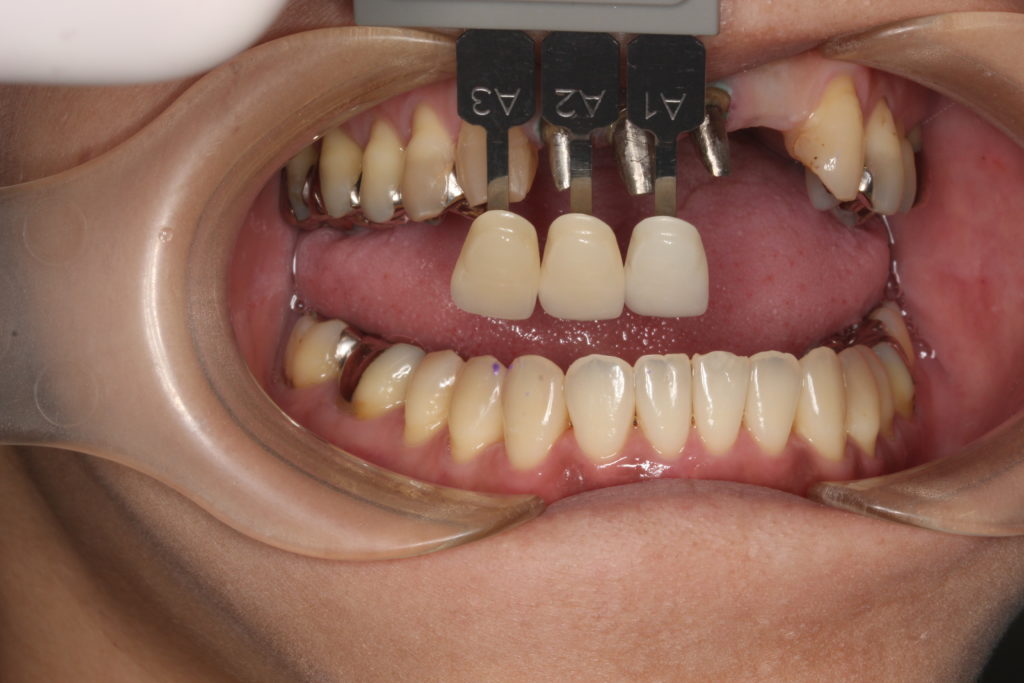

歯の色見本で、周囲の歯の色に合わせます。

人それぞれ歯の色が違います。指紋のようなものですね。

また歯の場所によっても色は違い、1本1本グラデーションが出ていています。

下の歯の色も参考にします。

お口の中、前歯の色味のバランスを考えて合わせていきます。

当院では自費専門の技工士がその方に合った歯を製作します。

材質はジルコニアセラミックを使い、綺麗に仕上げます。